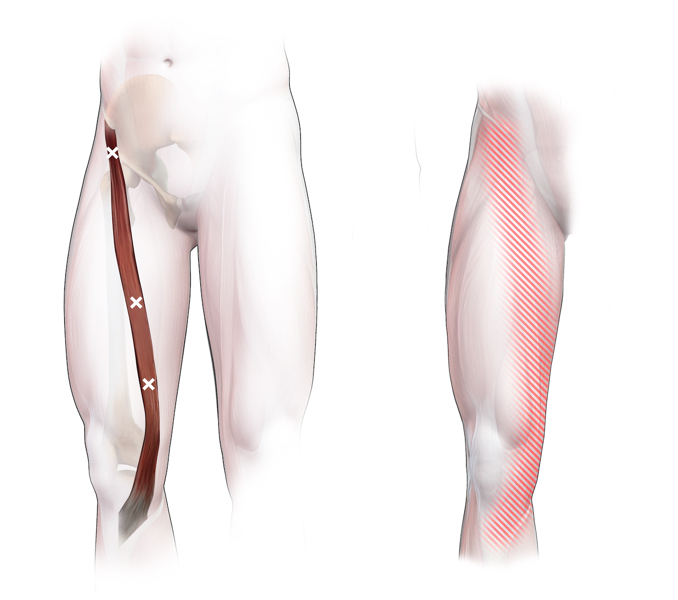

Spieren (Nederlands)

Spieren (nederlands)

Spieren (Latijn)

Spieren (latijn)